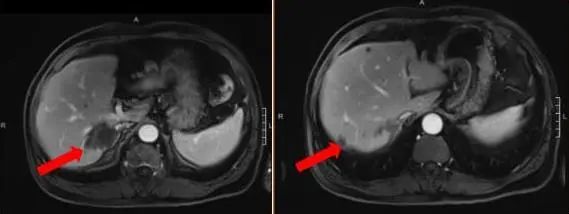

腹部增强MRI:胃壁增厚并腹腔内多发肿大淋巴结(较大者直径约2.6cm),考虑胃Ca并淋巴结转移;肝内多发异常信号灶,考虑转移瘤,6.4*7.8cm。

图1 腹部增强MRI